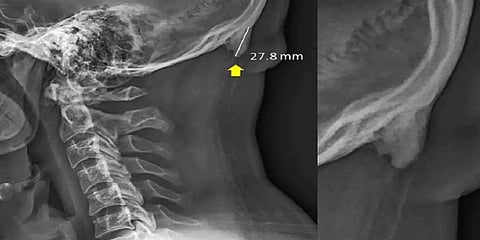

செல்போனை அதிக நேரம் குனிந்தபடியே பயன்படுத்தி வருவதால் தலையின் பின்புறம் உள்ள மண்டை ஓட்டுக்குள் கூர்மையான எலும்பு ஒன்று வளர்வதாக விஞ்ஞானிகள் கண்டுபிடித்துள்ளனர். இது தொடர்பாக தெரிவித்துள்ள விஞ்ஞானிகள், அதிக நேரம் குனிந்தபடியே பயன்படுத்துவதால் தலையின் முழு எடையும் மண்டை ஓட்டின் பின்புறம் செல்கிறது.

இதனால் தசை நாண்கள், தசை நார்கள் வளர்கின்றன. இதன் காரணமாக தலையின் பின்புறம் உள்ள மண்டை ஓட்டுக்குள் கூர்மையான எலும்பு ஒன்று வளர்கிறது என்று தெரிவித்துள்ளனர்.